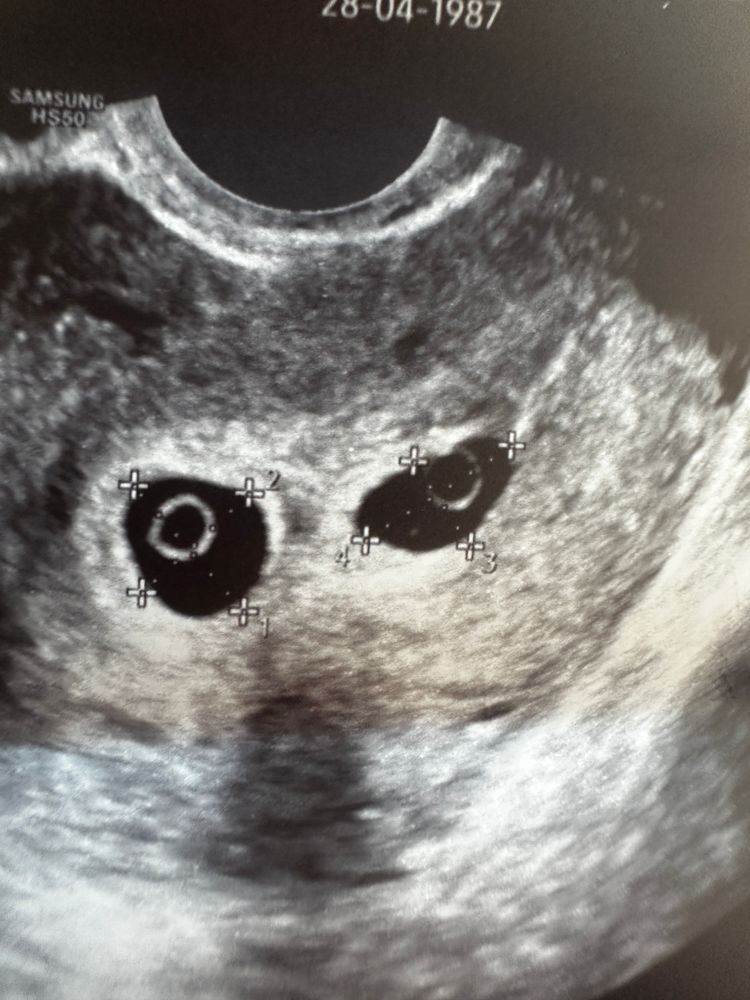

Первая беременность в 37 лет, двойня

По узи похоже на волка) но врач говорит, скорее всего один замирает. Возможно и оба. Но ждем и надеемся!🤞 Изображение

Хгч растет вообще непонятно и плохо...особенно с двойней. А по узи вроде и нормально все.

35.5 недель Один эмбрион из двойни замер, 7 недель 5 дней